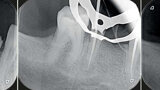

Fig. 8 : Cas clinique Dr Camille Bertrand.

Fig. 9 : Cas clinique Dr Camille Bertrand.

Fig. 10 : Cas clinique Dr Camille Bertrand.